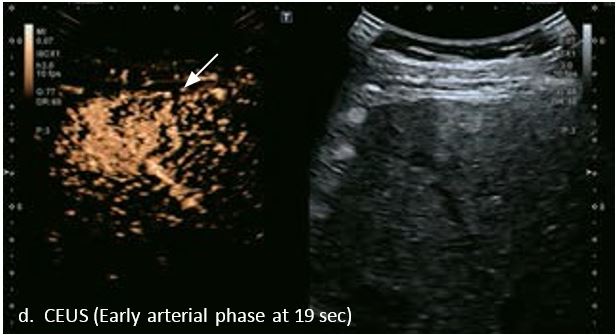

Оцінка результатів лікування ГЦК

Проведено повторне обстеження 79-річного чоловіка з цирозом печінки В, ускладненим ГЦК, після транс-артеріальної хіміоемболізації (ТАХЕ). Було виявлено нове ураження, розташоване поруч з ураженням після ТАХЕ. На сірошкальному зображенні чітко видно нове ураження, але складно виявити рецидив ГЦК в зоні ураження після ТАХЕ. За допомогою кольорового картування SMI (cSMI) можна побачити розвинену судинну мережу всередині нового вогнища ураження. Для оцінки результату лікування було виконано CEUS. За допомогою CEUS можна легко дослідити як нове ураження, так і рецидив ГЦК у вогнищі ураження після TACE. Нове ураження демонструє гіперпосилення артеріальної фази і відсутність вимивання до 5 хвилин, отже, це ураження LI-RADS 4, ймовірна ГЦК за критеріями LI-RADS. Підживлюючі судини можна чітко спостерігати в ранній артеріальній фазі. Для ураження після TACE, більша його частина не підсилюється, однак, в артеріальній фазі спостерігається ділянка гіперпосилення у верхній частині лікованого ураження, що вказує на рецидив ГЦК.